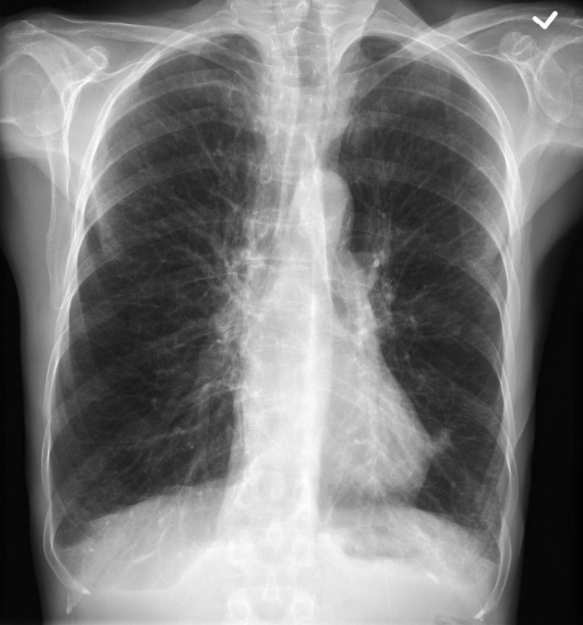

What does this scan show?

CXR demonstrating COPD with hyperinflation

Chest x-ray (CXR):

Hyperexpanded

Flattened hemidiaphragms

Hypodense

Saber-sheath trachea